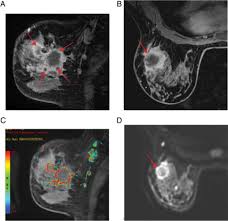

Can Ct Scan With Contrast Detect Breast Cancer - Breast Lumps Diagnosis Evaluation And Treatment : The cancer develops when abnormal cells crowd out healthy ones, potentially causing a lump in the breast or a bloody discharge from the nipples.. Breast cancer affects over 200,000 women each year. Luckily, i was still diagnosed pretty early. A ct scan is also called computerized axial tomography (cat) scan. In contrast with bone scans, which are only able to detect bone metastases, pet/ct has the advantage of concurrently imaging other common sites of breast cancer metastases such as the liver and lungs, says lead author patrick morris, a breast cancer specialist at memorial sloan kettering. This is an excellent way to take a needle biopsy for inflammatory breast cancer because imaging can show the best place to take the biopsy.

Learn the stage of your cancer. The term tomography comes from the greek words tomos (a cut, a slice, or a section) and graphein (to write or record). In contrast with bone scans, which are only able to detect bone metastases, pet/ct has the advantage of concurrently imaging other common sites of breast cancer metastases such as the liver and lungs, says lead author patrick morris, a breast cancer specialist at memorial sloan kettering. This is an excellent way to take a needle biopsy for inflammatory breast cancer because imaging can show the best place to take the biopsy. Ct scans are most often done as an outpatient procedure.

A ct scan is one of the most frequently utilized exams to detect cancer and to show things such as a tumor's shape and size.

This test is most often used to look at the chest and/or belly (abdomen) to see if breast cancer has spread to other organs. Not necessarily is the whole body going to be scanned at that time. Once a nodule is found, a workup is done to see if it is cancer. If i had contrast on the earlier ct, my cancer would have been found 2 1/2 years earlier. Help check how well treatment is working and/or.

Ct scans can help doctors: If you have a large breast cancer, your doctor may order a ct scan to assess whether or not the cancer has moved into the chest wall. This substance is often called a tracer, because it helps reveal cancer in the body. The scan lets them:learn the cancer's stage. Computed tomography scan, ct scan, cat scan, and spiral or helical ct. 234 views answered >2 years ago Before the scan, you will either drink a liquid dye or be given an injection of dye into a vein in your arm. Breast cancer affects over 200,000 women each year. A pelvic ct scan can be used to detect several types of cancer. Contrast medium is a dye that helps body tissues show up more clearly on the scan. In contrast with bone scans, which are only able to detect bone metastases, pet/ct has the advantage of concurrently imaging other common sites of breast cancer metastases such as the liver and lungs, says lead author patrick morris, a breast cancer specialist at memorial sloan kettering. You are encouraged to drink clear liquids. This helps determine whether or not the cancer can be removed with mastectomy.

In general breast cancer can be detected on a routine chest ct scan regardless of if contrast media is used or not. Several types of cancer can form in the breast, making it the second most common cancer that affects american women. These scans expose you to more. Before a pet/ct scan, an iv that injects a small amount of a radioactive substance will be placed into one of your veins. Long story short i have a ct scan with contrast on 1st june to look for cancer in the abdominal cavity.

Advanced Radiology Consultants Fast Breast Mri from www.adrad.com The term tomography comes from the greek words tomos (a cut, a slice, or a section) and graphein (to write or record). They may also use it to learn more about the cancer after they find it. If i had contrast on the earlier ct, my cancer would have been found 2 1/2 years earlier. When a ct scan misses cancer. Breast cancer affects over 200,000 women each year. If you have a large breast cancer, your doctor may order a ct scan to assess whether or not the cancer has moved into the chest wall. A ct scan may be used to: Therefore, ct scans can lead to a false negative this can negatively impact your ability to get any treatment at all this can prolong the time it takes you to access treatment